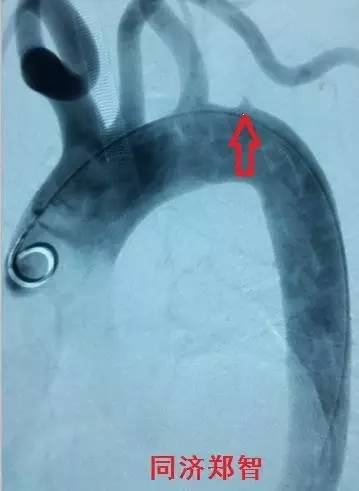

三维重建显示主动脉弓穿透性溃疡,与图11为同一病人(图12)。

图12